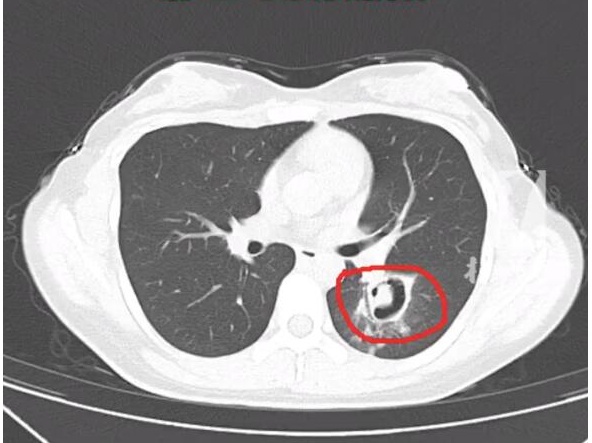

一个星期前,在杭州居住的一位00后的王小姐(化名)开始出现咳嗽、乏力和高烧,体温最高达到了40度。情况严重,王小姐被朋友送至附近的杭州师范大学附属医院。通过一系列检查,医生在肺部CT上发现,王小姐的肺部有多个“小树芽”,疑似是霉菌性肺炎。王小姐透露,一个月前她发现家中衣橱有霉点,进行清理时没有做好防护措施,吸入了大量扬起的杂质和灰尘。随后出现了阵发性咳嗽,虽然轻微但被忽视了。在了解情况后,医生给她做了纤维支气管镜检查,发现气道壁上有大量白色霉菌斑点,化验确认为曲霉菌。